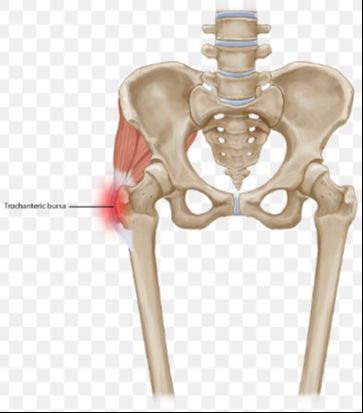

My doctor has identified two potential causes for my discomfort, with the first being trochanteric bursitis. This condition involves inflammation of the bursa sack on the outer side of the hip. Several rotator-type muscles of the hip attach to the trochanter, facilitating inward and outward leg rotation. Additionally, the IT (iliotibial) band connects to this area. The IT band, akin to a ligament, originates from the pelvis and extends along the outer thigh to the top of the shinbone (tibia). During activities like running, the IT band acts as a reservoir for energy, aiding in leg propulsion and swing as it tightens when the leg moves backward and releases energy as the foot leaves the ground.